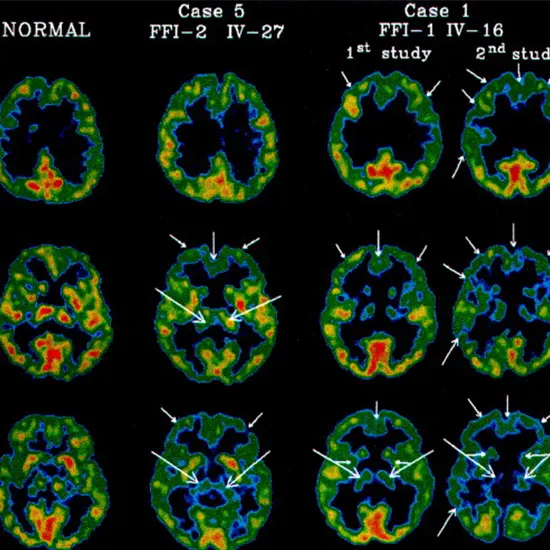

Imaging Studies

The diagnosis of fatal familial insomnia (FFI) may be aided by the use of brain imaging methods like positron emission tomography (PET) and magnetic resonance imaging (MRI). These examinations enable medical professionals to examine the composition and operation of the brain and spot any anomalies that could point to FFI.